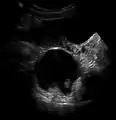

- A complex cyst due to a dermoid as seen on ultrasound